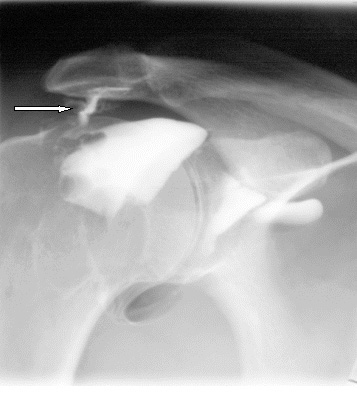

Zespół zamrożonego (bolesnego) barku (Choroba Duplaya) to nie jedna, ale wiele chorób dotyczących barku. Przyczyną bólu i ograniczenia zakresu ruchów ręką może być przeciążenie mięśni, szkodzenie ścięgna lub zapalenie kaletki podbarkowej. Główny symptom zespołu bolesnego barku to ból. Bywa, że początkowo jest niewielki, pojawia się tylko przy unoszeniu ręki powyżej linii ramion. Z czasem się nasila i dokucza także przy innych ruchach kończyną. Zdarza się też, że zjawia się nagle, np. po wykonaniu gwałtownego ruchu, i jest tak ostry i silny, że rękę cały czas trzymamy w jednej pozycji, aby uniknąć cierpienia. Bólowi może towarzyszyć obrzęk okolicy barku. Jeśli zlekceważymy te dwa objawy, dołącza trzeci – znaczne ograniczenie zakresu ruchów w stawie ramiennym. Źródłem dolegliwości są najczęściej: 1. przeciążenie mięśni, 2. urazy ścięgien, 3. zapalenie kaletki podbarkowej, 4. choroby reumatyczne (RZS, choroba zwyrodnieniowa stawów) lub neurologiczne (zapalenie splotu szyjnego i ramiennego). Do zespołu bolesnego barku dochodzi podczas czynności wymagających uniesienia ręki powyżej linii ramion, których nie wykonujemy na co dzień (np. mycie okien) lub przenoszenia ciężkich przedmiotów. Powodują go także powtarzające się, jednostajne ruchy, spanie w niewygodnej pozycji, gwałtowne szarpnięcie ręką czy zbyt intensywne ćwiczenia, dlatego tak często występuje u sportowców, szczególnie tych którzy wykonują powtarzalne rzuty. Źródłem bólu barku może być uszkodzenie ścięgien 4 małych mięśni (podgrzebieniowy, nadgrzebieniowy, podłopatkowy, obły mniejszy) tworzących tzw. stożek rotatorów. Ścięgna te otaczają głowę kości ramiennej i są zrośnięte z torebką stawową. Najczęściej dochodzi do uszkodzenia ścięgna mięśnia nadgrzebieniowego, np. podczas rzucania piłką. Ale przyczyną bólu bywa też uraz ścięgna mięśnia dwugłowego. Łatwo je naciągnąć nawet w trakcie tak banalnej czynności jak sięganie w samochodzie po torebkę leżącą na tylnym siedzeniu. Naciągnięcia i naderwania ścięgien kumulują się i mogą być przyczyną przewlekłego bólu barku, a nawet zerwania ścięgna. Zdarza się, że zespół bolesnego barku przechodzi w tzw. zespół ciasnoty podbarkowej. Schorzenie to konsekwencja stanu zapalnego spowodowanego długotrwałym drażnieniem ścięgien. Dolegliwość bardzo często dotyka młodych sportowców np. tenisistów lub pływaków.

Chory bark, w przeciwieństwie do większości urazów układu kostnego, nie może być unieruchomiony, aby nie doprowadzić do dalszego rozwoju choroby. Nasza innowacyjna orteza AM-SOB-05 powoduje, że dzięki jej zastosowaniu następuje pełne odciążenie stawów barkowych, bez ich unieruchomienia. Utrzymuje ona kość ramienną w panewce stawu. Dzięki naszej ortezie nie następuje dalszy postęp choroby, ustaje ból oraz wszelkie ograniczenia w swobodnym poruszaniu kończyną.

Zdarza się, że zespół bolesnego barku przechodzi w tzw. zespół ciasnoty podbarkowej. Schorzenie to konsekwencja stanu zapalnego spowodowanego długotrwałym drażnieniem ścięgien. Dolegliwość bardzo często dotyka młodych sportowców np. tenisistów lub pływaków.

Chory bark, w przeciwieństwie do większości urazów układu kostnego, nie może być unieruchomiony, aby nie doprowadzić do dalszego rozwoju choroby. Nasza innowacyjna orteza AM-SOB-05 powoduje, że dzięki jej zastosowaniu następuje pełne odciążenie stawów barkowych, bez ich unieruchomienia. Utrzymuje ona kość ramienną w panewce stawu. Dzięki naszej ortezie nie następuje dalszy postęp choroby, ustaje ból oraz wszelkie ograniczenia w swobodnym poruszaniu kończyną.